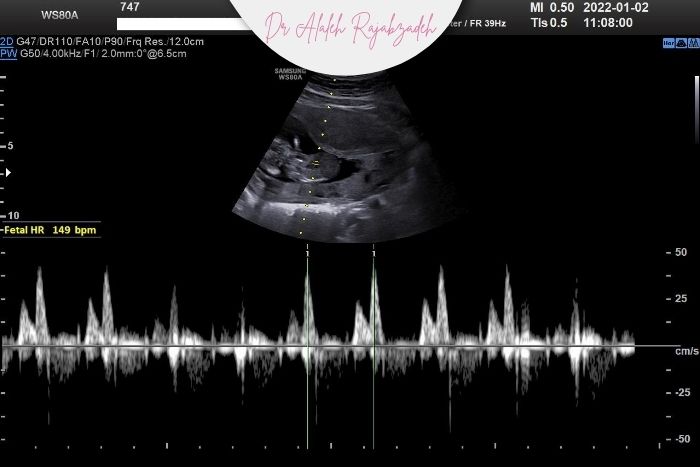

در چنین شرایطی پزشک معمولاً درخواست سونوگرافی فوری میدهد تا وضعیت ضربان قلب، حرکات جنین، جریان خون در بند ناف و عملکرد جفت بررسی شود.

در صورت نیاز آزمایش NST یا بیوفیزیکال پروفایل (BPP) نیز انجام میشود تا اطمینان حاصل شود جنین در شرایط ایمن قرار دارد.